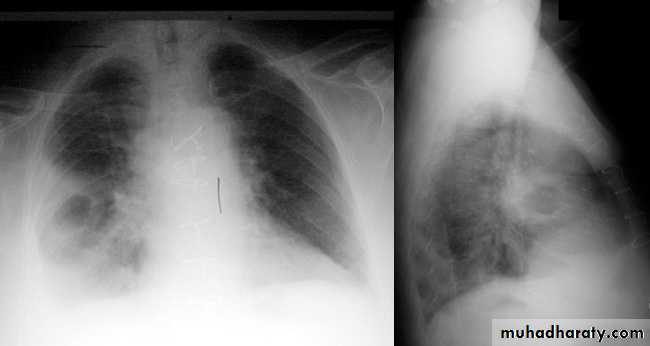

A chest X-ray is usually sufficient to confirm the clinical diagnosis of pneumonia.

In lobar pneumonia, a homogenous opacity localized to the affected lobe or segment usually appears within 12 – 18 hours of the onset of illness.

CT scan is rarely required, except for suspected underlying bronchial obstruction caused by tumour or foreign body.

Chest X-ray helps in:• Differentiating CAP from other diagnosis

• Provide information about severity (cavitation and multilobar involvement)

• Detects complications (pleural effusion or abscess formation).

• It can occasionally suggest an aetiological agent (pneumatocoele in Staphylococcus aureus pneumonia).